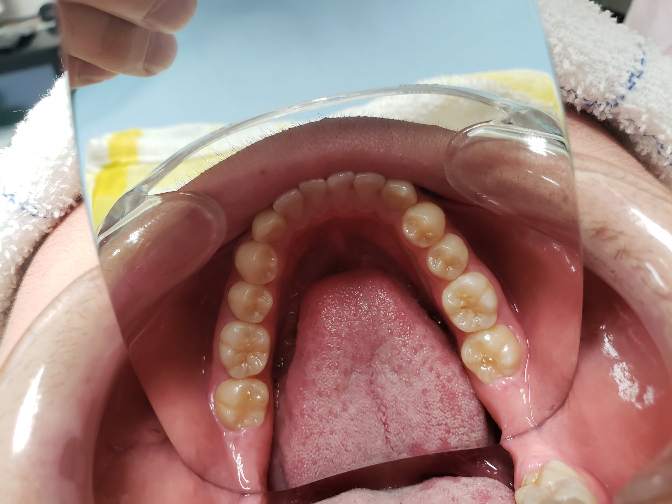

治療6年後

高校2年生で下の左右の埋伏の親知らずを抜歯しました。下の埋伏親知らずは、将来の歯並びの予後に悪い影響を与えたり、年齢が上がるにつれて抜きにくくなるので、できれば早期の抜歯が望ましいと考えています。一方、上の親知らずのは抜歯は簡単なことが多く、手前の7番や開咬などの不正咬合に悪い影響をあたえなければ、下程急ぐ必要はないかもしれません。当医院では一応下の親知らずの抜歯をもって、ある程度の矯正は終了と捉えています。しかし、管理されるのが嫌、抜きたくない方、他(高次機関等)で抜歯したいという方は13歳位で1期治療は終了という方針です。